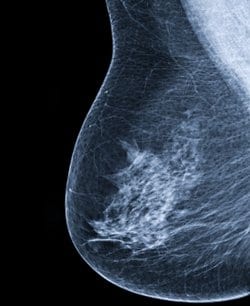

בחר בחוכמה: חמש פרוצדורות מהן ניתן להימנע במקרה של סרטן שד שפיר

ה- American Society of Breast Surgeons פרסמה רשימה של חמש פרוצדורות או בדיקות מהן ניתן להימנע במקרה של סרטן שד שפיר. הרשימה היא חלק מהקמפיין Choosing Wisely של ה- American Board of Internal Medicine.